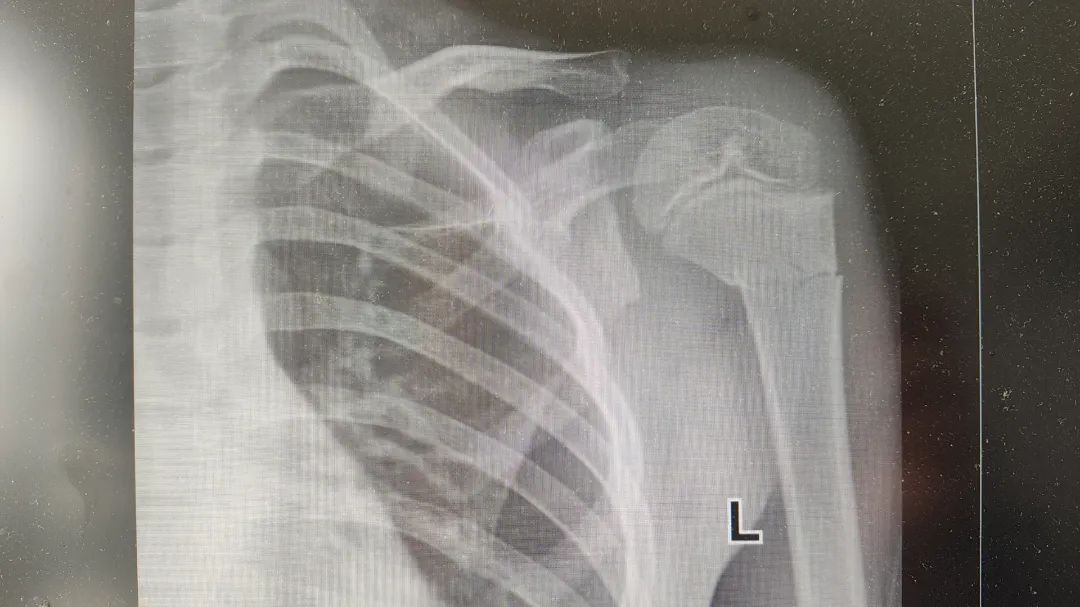

◆ ◆ ◆ ◆ 小辉(化名)今年7岁,在家玩耍时不慎从沙发上摔下,伤后即感左上臂出现剧烈疼痛及肿胀伴有活动障碍。遂即来我院急诊科就诊,门诊医师行拍片示“左肱骨近段骨折”,门诊经结合外伤史、症状体征及相关影像学检查后拟以“左肱骨骨折”为诊断,收住骨科继续治疗。 (入院影像结果) 入院后,骨科主任尹绍猛立即组织团队进行病例讨论,考虑到小辉年龄较小,保守治疗效果欠佳且孩子遵从能力差,有骨折不愈合、畸形愈合等多种可能性,将会导致小辉以后生活有患肢短缩或畸形等情况,经骨科团队讨论后决定为小辉实施左肱骨近段骨折闭合复位+弹性髓内针内固定术。 术中,仅在小辉患肢开个约1cm的小口,对称插入两根弹性髓内针,利用钛合金或不锈钢良好的弹性恢复力作用于骨折,通过髓腔的3个接触点转换成推力和压力,从而使骨折复位。手术非常顺利,仅仅用了30分钟就完成了手术,术后小辉恢复良好,复查骨折断端对位对线良好,畸形纠正。 (术后影像结果) 尹绍猛主任介绍,弹性髓内针适应症广泛,多应用于3至13岁儿童长骨骨折。肥胖者降低年龄标准,消瘦者可适当提高年龄标准,但不宜超过15岁,其中5至10岁非肥胖者最佳,各类长骨新鲜单纯性骨折及干骺端闭合骨折,以横断和短斜形骨折最佳。此外还可应用在有足够骨皮质支撑的长斜形或螺旋形骨折。弹性髓内针技术属于微创闭合穿针内固定,骨折处没有切口,具有创伤小、操作简单、骨折复位满意、固定简便可靠,骨折愈合快,并发症少,住院时间短等特点。该技术已得到世界范围内小儿骨科医生的广泛推崇,成为治疗儿童长骨骨折的首选方法。 弹性髓内针技术的特点 1.创伤小、留疤小、伤口美观; 2.愈合快,住院时间短,不影响生活学习,骨折愈合后取出内固定简单,仅需切开皮下拔出即可,节省了时间和费用; 3.疗效好,骨折复位满意,固定简便可靠,对断端血供影响小,有利于骨痴生长。 4. 应用广,可应用于3至13岁儿童长骨骨折,其中5至10岁非肥胖者最佳。